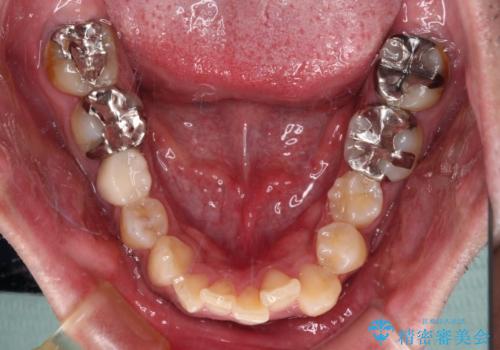

- 主張してる上の前歯を気にして来院された患者様です。

上の前歯が出ているものの、口元が出っ歯というわけではなかったため、非抜歯矯正にて治療を行うこととしました。

元々むし歯リスクが高かった上に、矯正治療中も磨き残しが多かったため、今後はむし歯治療を行う必要があります。